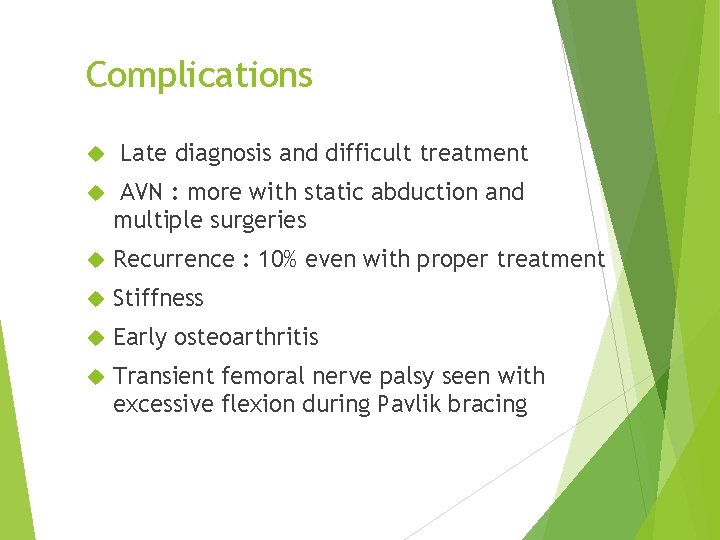

Complications Late diagnosis and difficult treatment AVN : more with static abduction and multiple surgeries Recurrence : 10% even with proper treatment Stiffness Early osteoarthritis Transient femoral nerve palsy seen with excessive flexion during Pavlik bracing